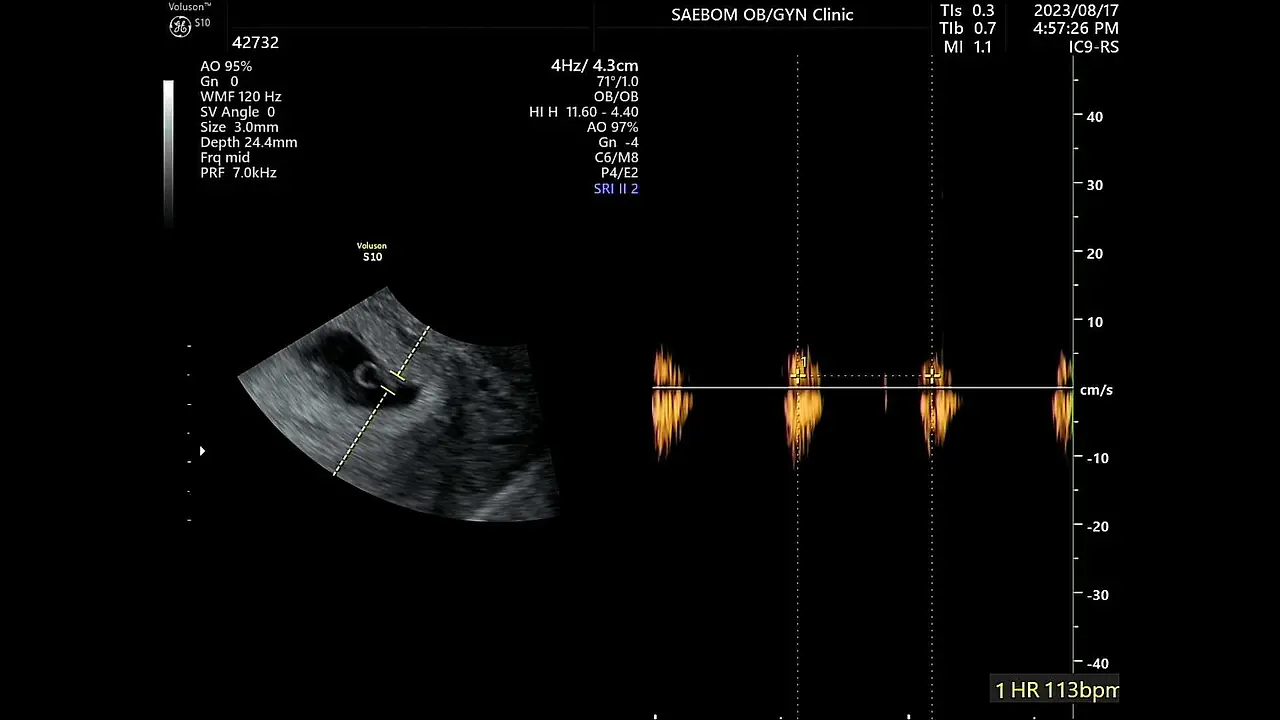

4주 차에 3mm 아기집을 아주 빠르게 확인했다.